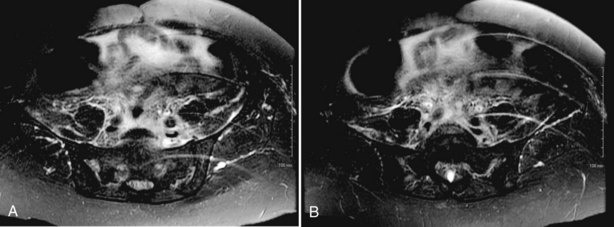

In most RPF patients, the clinical symptoms are generally nonspecific, and physical examination is usually unrevealing. Laboratory evaluation may reveal an elevated erythrocyte sedimentation rate, moderate leukocytosis, anemia, and variable renal insufficiency with associated electrolyte abnormalities. If the overall renal function is normal, an excretory urogram (EVU) or more commonly computed tomography (CT) with contrast may be performed. Typical EVU findings include hydronephrosis with medial deviation of the proximal ureter and midureter and a smoothly tapered ureter at the level of obstruction. Urinary obstruction is usually bilateral, but unilateral cases have been described. Uncommonly, there are patients with symptoms of urinary obstruction but little hydronephrosis on imaging. CT scan typically reveals hydronephrosis associated with a well-delineated retroperitoneal soft tissue mass enveloping the great vessels and the ureters (Fig. 41–36). If the patient has significant renal impairment, a retrograde pyelogram may be performed. In the radiographic evaluation of RPF, magnetic resonance imaging (MRI) can also be helpful because the mass itself has characteristic T1- and T2-weighted images. Retroperitoneal fibrosis is characterized as a diffusely low signal intensity on T1-weighted imaging, although the T2 signal may vary considerably, with high signal intensity consistent with active disease (Fig. 41–37A and B). With treatment, T2 signal often diminishes and thus provides a measure of therapeutic efficacy. Moreover, gadolinium enhancement may also prove valuable in assessing the response to treatment because associated decreases in gadolinium contrast enhancement should also be expected following appropriate therapy (Cronin et al, 2008). If a kidney is suspected to be nonfunctioning, differential renography should be considered to determine renal function because it may affect surgical planning. Representative biopsies of the mass should be obtained percutaneously or at the time of open or laparoscopic ureterolysis to rule out malignancy and allow one to proceed with treatment for RPF.